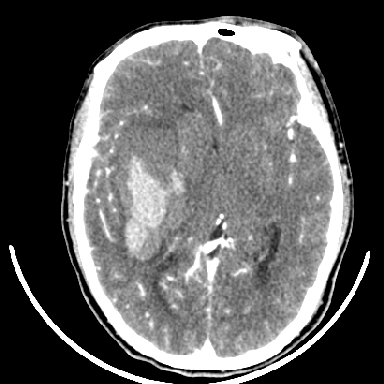

标题: CT6056:脑出血(血管畸形?) [打印本页]

标题: CT6056:脑出血(血管畸形?)

m 40突发头痛左侧偏瘫3小时

考虑高血压性脑出血,依据:

1是高血压性脑出血的好发部位,形态呈肾形,是高血压性脑出血的常见形状

2增强时占位效应加重了,考虑出血还没有停止

3病灶周围水肿不是太厉害,一般肿瘤出血水肿多非常明显

4病灶周围的‘软组织’影没有明显的强化

5至于脑血管畸形引起的出血,暂时没有看到明显的畸形血管影,也不太支持

支持右侧基底节脑出血

右侧基底节区脑出血.

支持右侧基底节区(主要为外囊区)原发性脑出血。

另附部分资料:“血液溢出血管外形成血肿,其内含有大量血红蛋白、血浆白蛋白,球蛋白,因这些蛋白对x线的吸收系数高于脑质,故ct呈现高密度阴影,ct值达40~90h,最初高密度灶呈非均匀一致性,中心密度更高,新鲜出血灶边缘不清。基底节区血肿多为“肾”型,内侧凹陷,外侧膨隆,因外侧裂阻力较小,故向外凸,其它部位血肿多呈尖圆形或不规则形”

术中抽出40ml陈旧血液,血肿底部似见一条索血管影